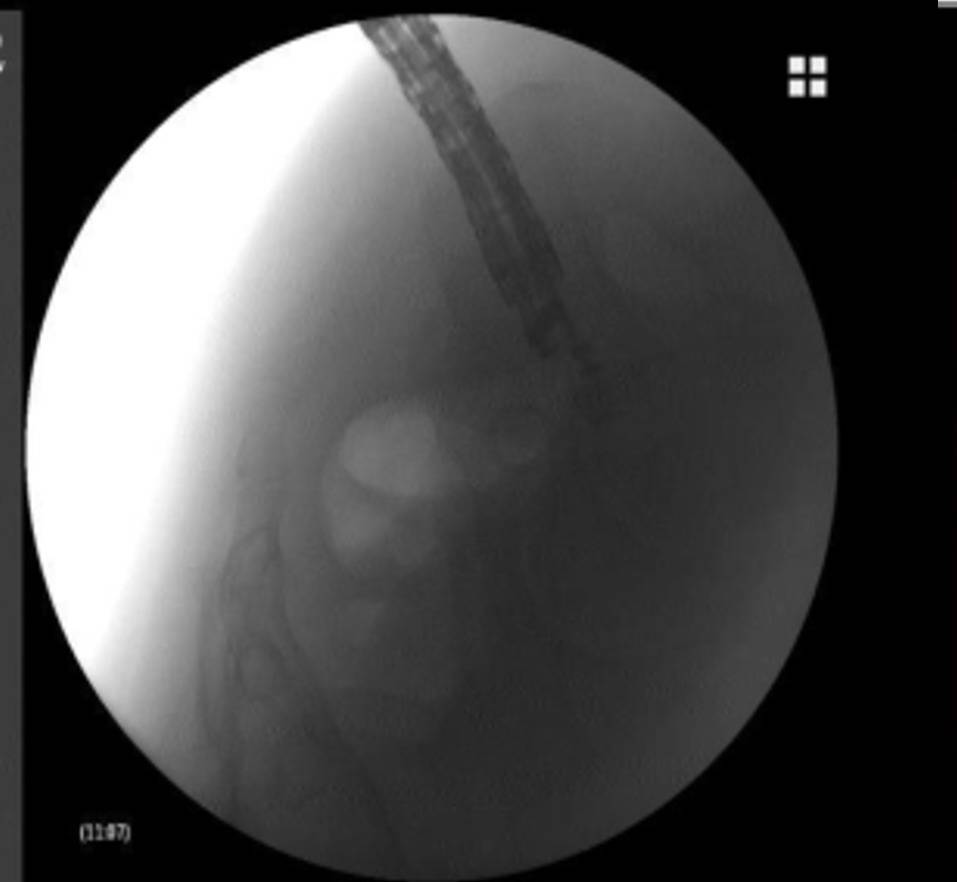

支架置入过程

术前CT显示直肠前方一直径5cm圆形脓肿